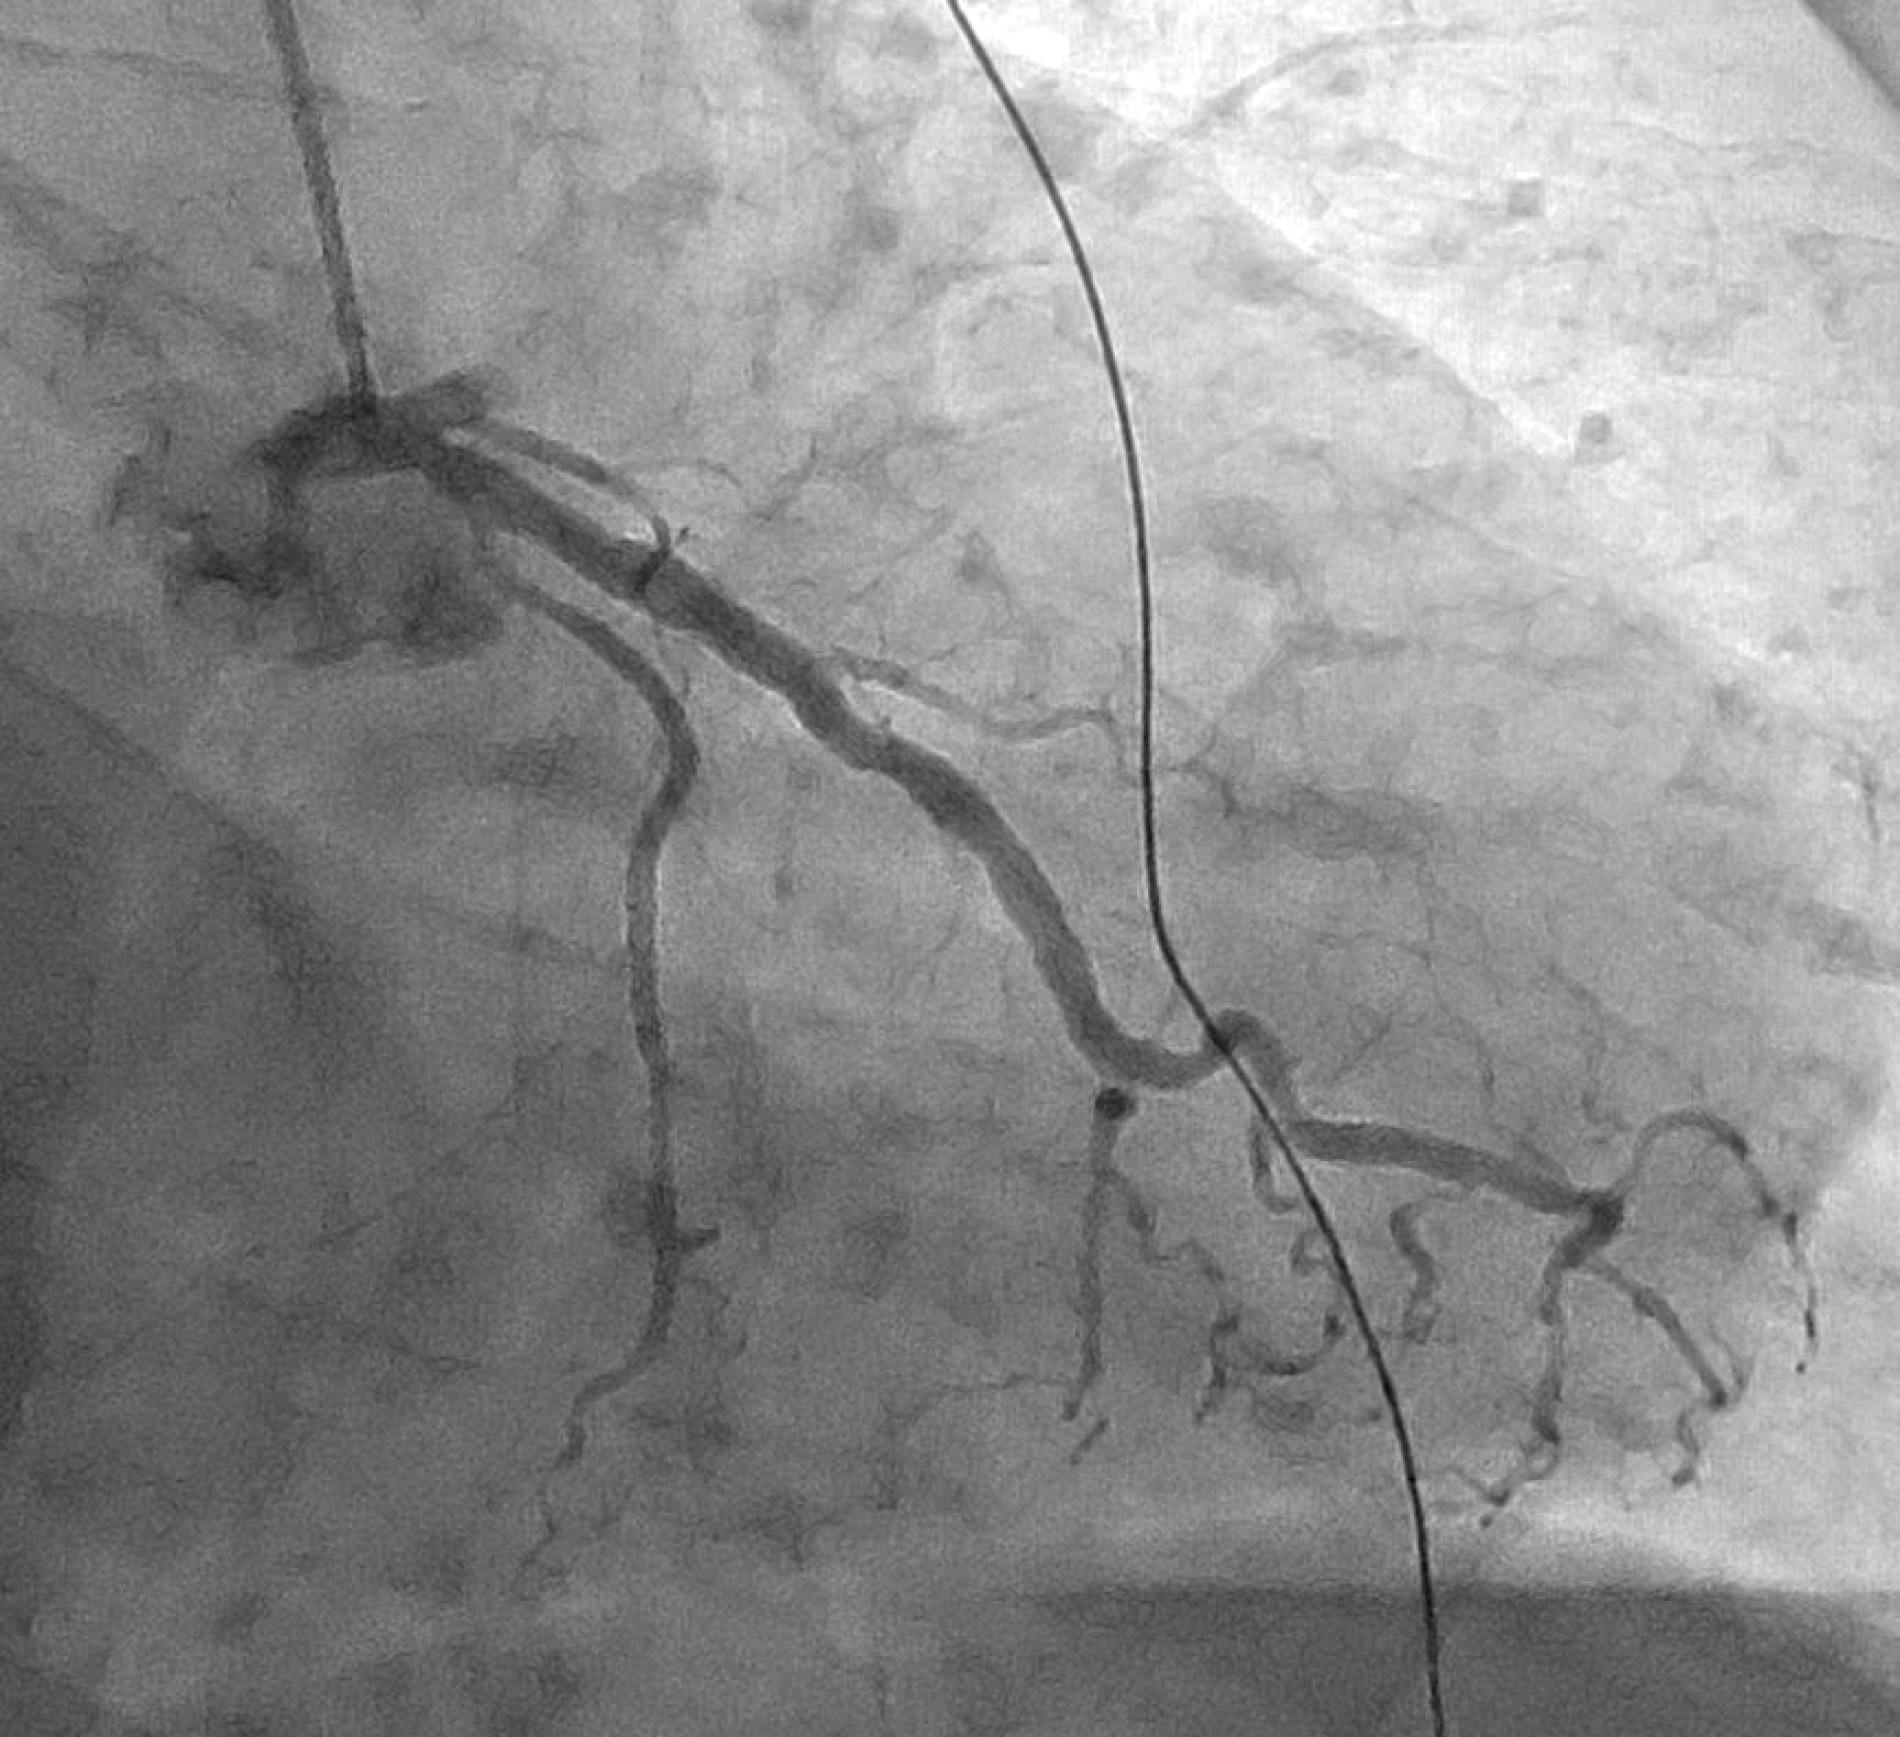

In the dominant RCA, a proximal aneurysm was present, associated with an ulcerated plaque and a severe stenosis in the distal part of the aneurysm. The aneurysmatic RCA was also characterized by a grade 4 thrombus (Figure 1).

Figure 1. Preprocedural angiogram of the left PA.